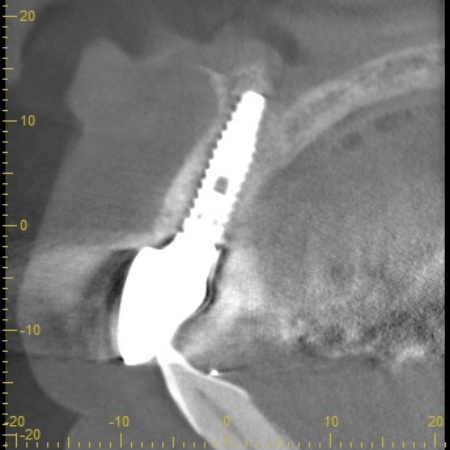

まずは歯根が折れた右上前歯を抜き、その直後にインプラントの埋入手術を行います。これは抜歯即時埋入といい、治療期間の短縮が期待できる方法です。

手術の際は、インプラント周囲の骨を強化するための骨移植と、歯肉の厚みを確保するための歯肉移植を併せて行いました。この処置により、インプラントの長期的な維持と、自然な歯肉のラインの実現を目指します。

インプラントを埋入しました。

骨と歯肉の移植を行いました。